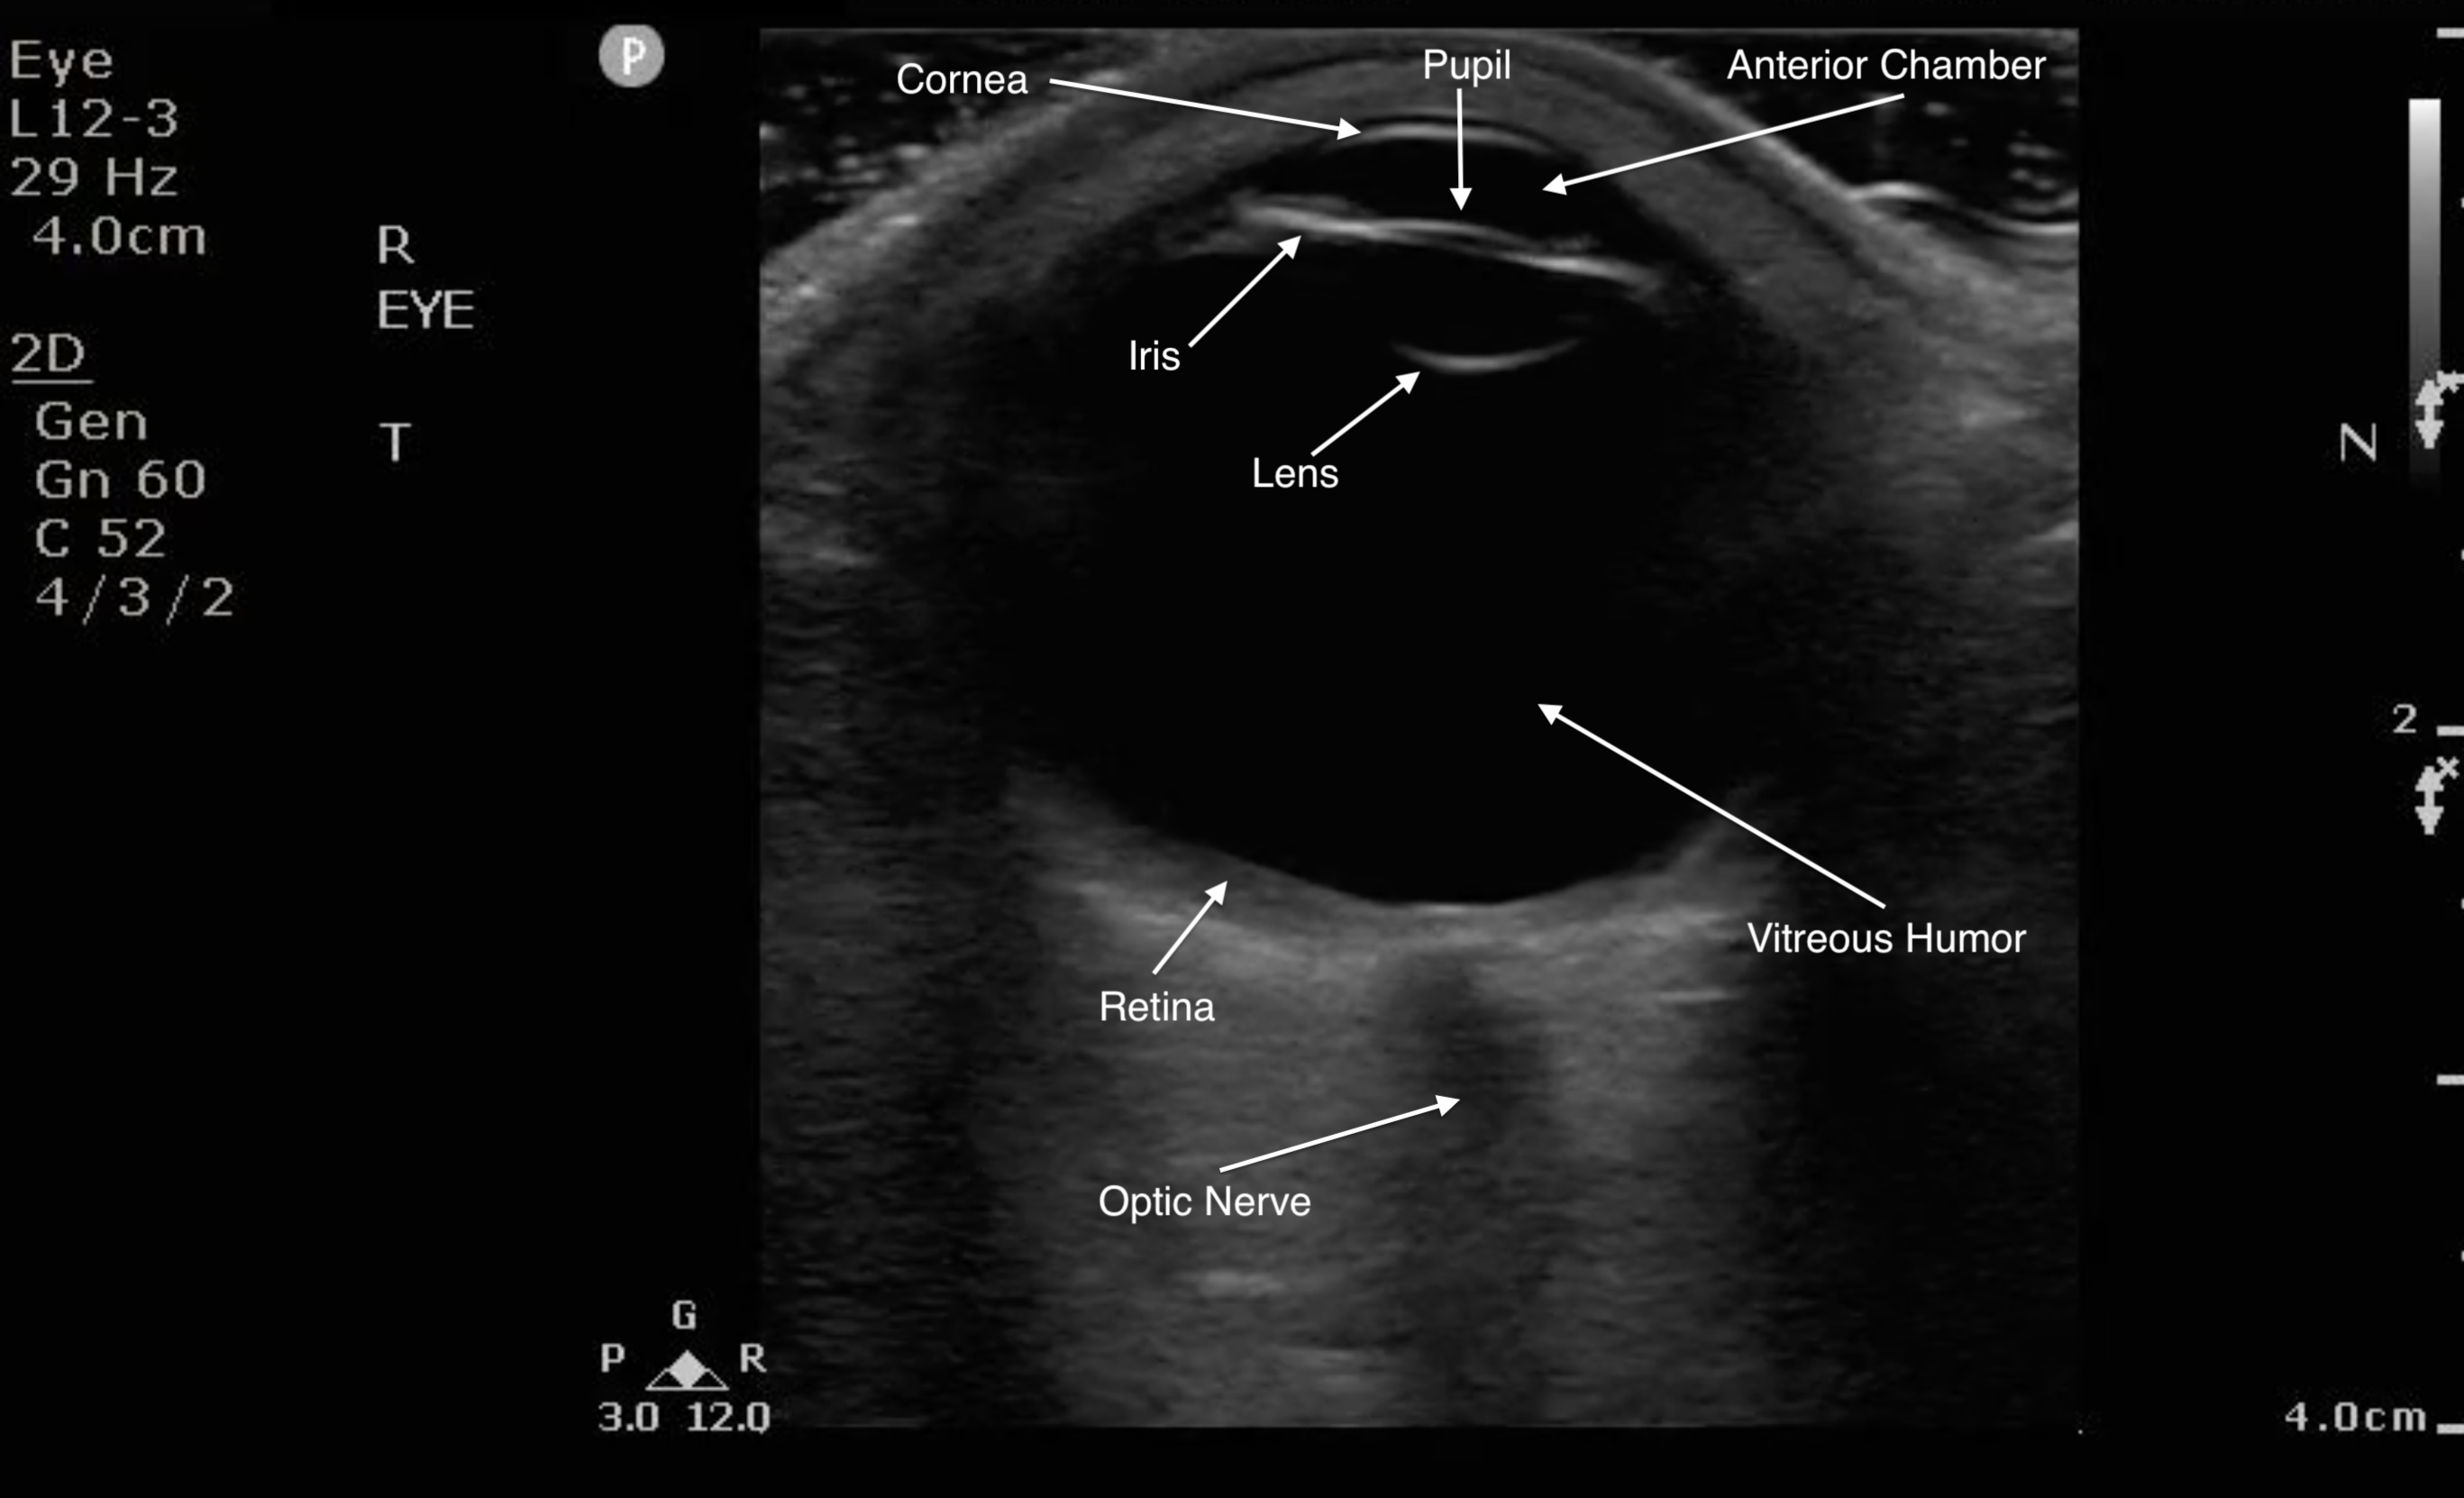

Figure 1. Sonographic eye anatomy

- Because the ocular chamber is fluid-filled, under ultrasound, it will appear as a round, anechoic structure.

- The most anterior structure seen, after the layer of ultrasound gel, is the eyelid.

- Just deep to the eyelid is the cornea and the anterior chamber. If too much pressure is applied during the ocular ultrasound examination, the anterior chamber may become compressed. It is important to avoid applying direct pressure to the eyelid.

- If the patient attempts to look down during the exam, you may be able to visualize the iris and pupil.

- The lens appears as a hyperechoic, curved line, located deep to the iris. If the patient has undergone cataract surgery, you may see two thin, hyperechoic parallel lines instead of the concave hyperechoic line.

- Normal vitreous humor will appear anechoic.

- The vitreous, retina, and choroid are located along the inside of the globe. Normally, you cannot differentiate one from the other.

- The most far field identifiable structure is the optic nerve. The parallel hyperechoic lines are the optic nerve sheath, since the optic nerve is hypoechoic and nondistinctive.

- Figure 3. Ultrasound image of a normal eye.